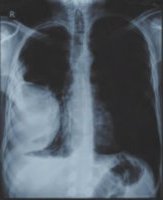

![]() Рис.1 |

Так или иначе состояние улучшилось настолько, что у меня хватило физических сил наконец-то пройти полное медицинское обследование. Результаты были удручающими, первый же рентгеновский снимок (рис. 1) показал наличие опухоли в лёгком размером с грейпфрут, последующая компьютерная томография показало эту опухоль уже во всей красе (рис. 2). Помимо опухоли, на снимках видно, что заболеванием была полностью затронута печень, именно поэтому организм перестал принимать и перерабатывать пищу. Врачи в один голос требовали срочного оперативного вмешательства. Был поставлен предварительный диагноз – рак, для подтверждения, которого необходимо было провести биопсию, от которой я отказался. Кроме того, мой отказ был мотивирован еще и тем, что вопреки всем исследованиям, по личным ощущениям моё состояние с каждым днем становилось всё лучше.